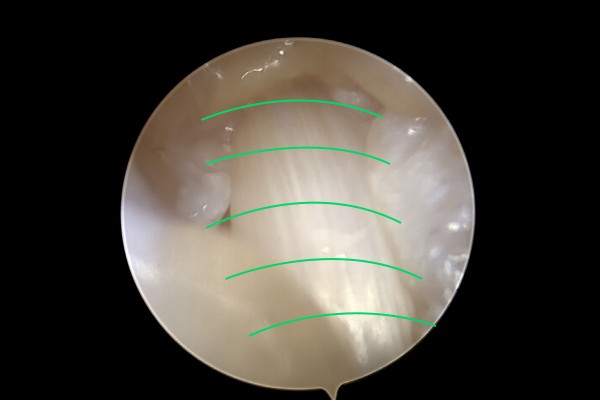

내시경 화면을 보면 손가락 힘줄을 덮어 압박하는 힘줄덮개(A1 활차)를 확인할 수 있습니다. 수술기구 진입을 위해 힘줄덮개를 살짝 터줍니다.

진입로로 진입 후 힘줄덮개를 좌/우로 나눠주어 힘줄에 가해지는 압박을 해소합니다.